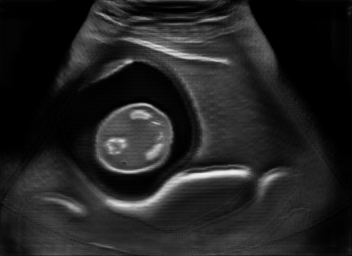

US simulation. We used a ray-tracing framework to render B-mode images from a geometric fetal model, by simulating a convex probe placed at multiple locations and orientations on the abdominal surface, with imaging settings listed in Tab 1. At each location, simply rasterizing a cross-section through the triangulated anatomical surfaces at the ultrasound center imaging plane provided corresponding semantic maps. Fig. 3 shows example B-mode images with corresponding semantic maps. A total of simulated frames were resized to and randomly split into training-validation-test sets by 80-10-10%.